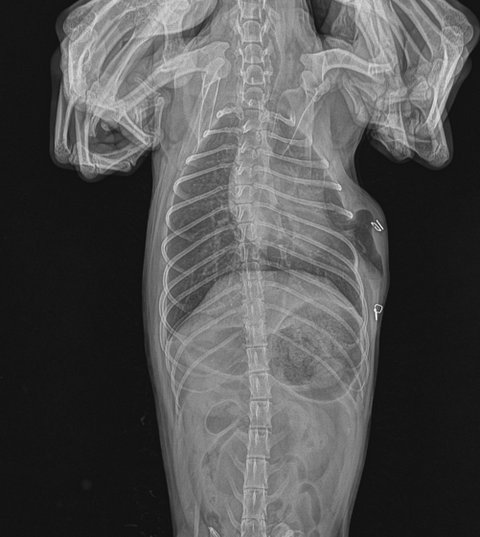

한마리는 큰 개에 물려 피범벅이 되었고,폐에 구멍이 뚫려 기흉이 생기며 수술을 하러 병원에 옮겨졌지만 결국 무지개다리를 건넜고 한마리는 아직도 큰 상처가 몸에 남아 치료중이며